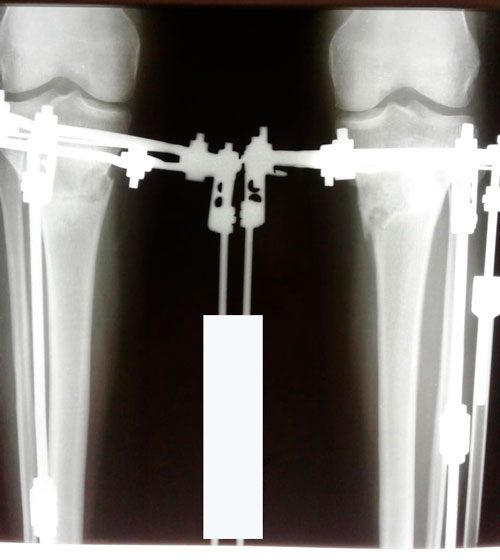

Исходник - 29 лет. Актобе.

Дата операции 15.05.2018г.

Двойная ротация, преимущественно справа.

Дата снятия аппаратов 01.08.2018г.

Срок сращения 75 дней.